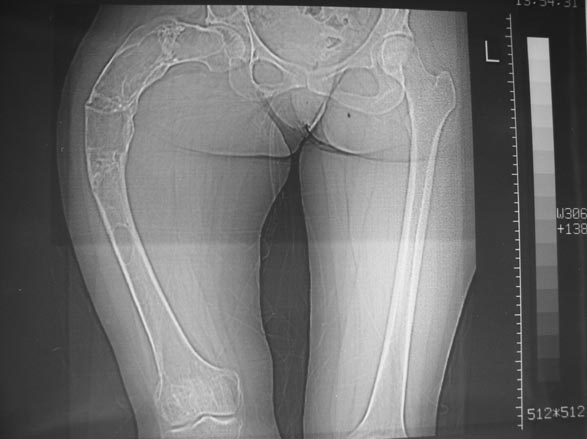

Женщина 28 лет, Больна с 12 летнего возраста, Когда после адекватной травмы получила перелом бедра. На рентгенограммах выявлено какое-то (рентгенограмм и документов нет) изменение бедренной кости, была оперирована, имеется гистологическое заключение - фиброзная дисплазия.дСформировалась деформация бедра. На сегодня - Укорочение 7см. Грубая деформация бедра по типу "пастушьей палки", последний патологический перелом в январе 2004г., консолидировавшийся при консервативном лечении. Имеются грубые изменения и в надвертлужном массиве.-- С уважением, Leonid

Собственно сустав не беспокоит, объем движений полный. По скиаграммам получается, что достаточно одной остеотомии на вершине деформации, чтобы восстановить длину и вывести коленный сустав в нужное положение.